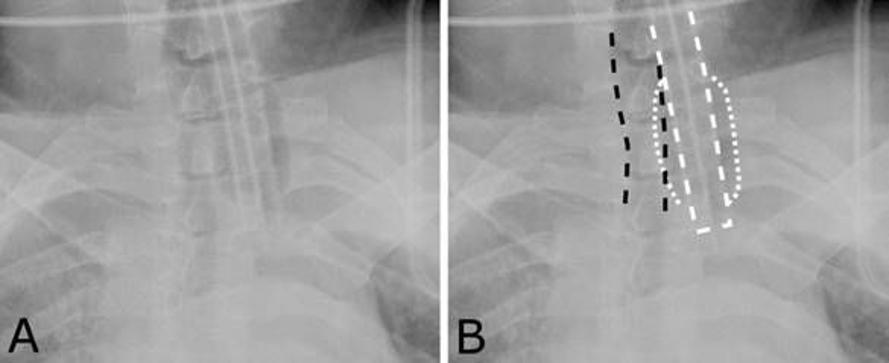

식도삽관(Esophageal Intubation)된 소아의 X-ray 사진 예 <출처: chestxray.hpage.co.in>

기관삽관이 식도와 같은 다른 구조물로 삽관되면 다량의 공기가 위를 채워 환자의 상복부가 부풀어 오르게 된다.

이 때 위관을 이용해 흡인하면 다량의 공기가 배출되면서 부풀었던 상복부가 가라앉는 현상을 보인다.